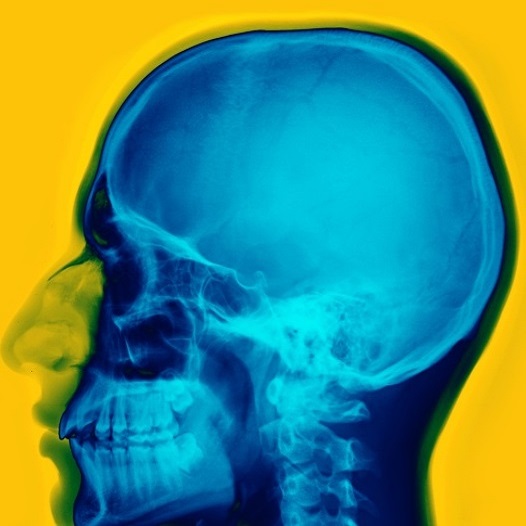

Вес мозга человека равен 2 % от общего веса тела, при этом мозг расходует 20 % всего полученного телом кислорода и углеводов.

Во время сна мозг гораздо более активен, чем во время бодрствования. Он обрабатывает полученные за день воспоминания, избавляется от токсинов и даже принимает решения.